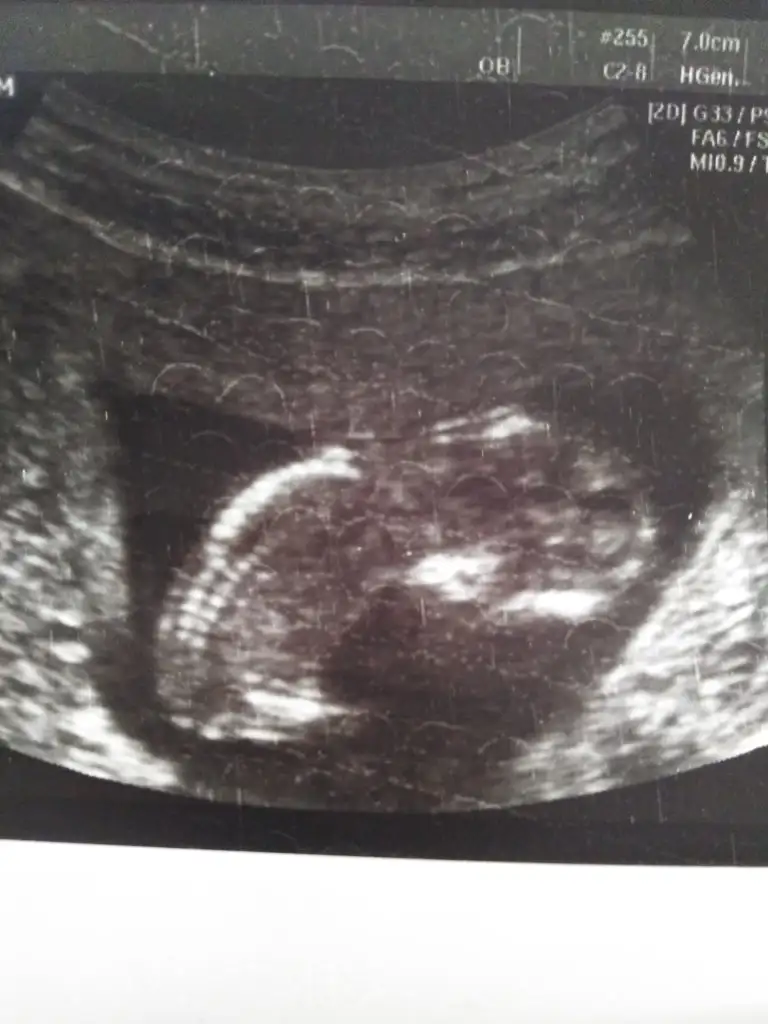

11 haftalık görüntüsü var mı cinsiyeti tahmin edecek olan☺️

Eklentiler

• 1C1E58D1-FC79-46C4-BA5E-4FDC4D5BE422.webp

1C1E58D1-FC79-46C4-BA5E-4FDC4D5BE422.webp

27,8 KB · Görüntüleme: 88

• 6D68836D-1FAE-42B4-9041-378E4BF167FA.webp

6D68836D-1FAE-42B4-9041-378E4BF167FA.webp

26,4 KB · Görüntüleme: 84

Benn bebişe de bakar mısınız yatmamış ama belki çözen olur

• IMG_20191031_120120.webp

IMG_20191031_120120.webp

28,2 KB · Görüntüleme: 62